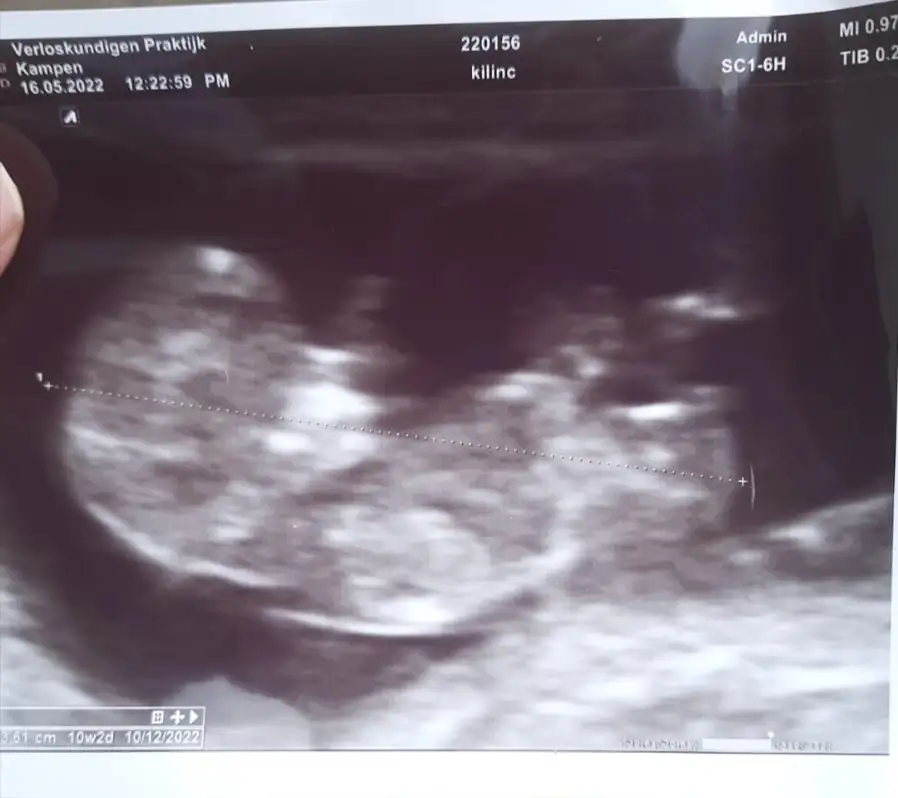

Banada tahmin yaparmisinjz 17+3

Eklentiler